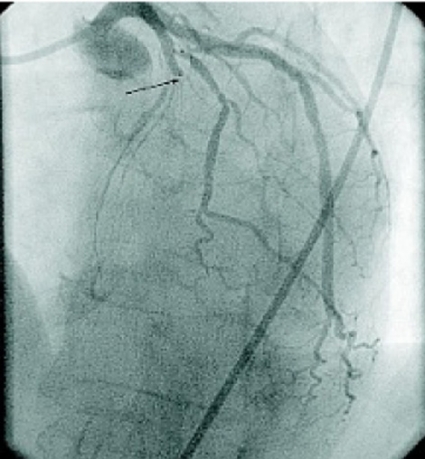

I jämförelsen mellan PCI och trombolys vid hjärtinfarkt med ST-förhöjning kan man ställa sig frågan varför PCI inte i större utsträckning påverkar mortaliteten, då metoden återskapar ett bra flöde (TIMI 3) i kranskärlet i 70–90 procent av fallen [12-14] och den bästa trombolysregimen i 50 procent [17]. Om man extrapolerar resultaten från den angiografiska substudien i GUSTO I [17] borde ett bra flöde i det infarktrelaterade kranskärlet resultera i en mortalitet på ca 5 procent, vilket antyder att det finns utvecklingsmöjligheter för PCI-tekniken.